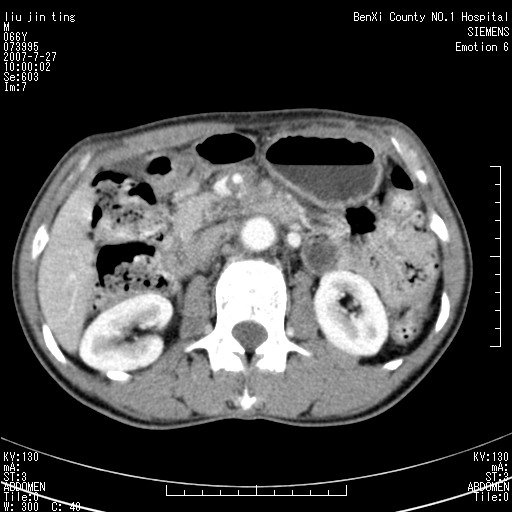

沿着肠系膜上动脉呈匍匐性生长的软组织肿块,形态不规则,包绕肠系膜上动脉,呈明显强化,考虑来源于肠系膜的恶性肿瘤

肠系膜根部肿块,累及肠系膜上动脉,考虑肿大淋巴结累及肠系膜上动脉.

腹腔干至肠系膜上动脉水平肿大淋巴结影可能性大.

沿着肠系膜上动脉呈匍匐性生长的软组织肿块,形态不规则,包绕肠系膜上动脉,呈轻-中度强化,考虑来源于肠系膜的恶性肿瘤。

钩突是正常的,只见腹膜后淋巴结的肿大,考虑淋巴瘤或转移可能。

支持!恶性纤维组织细胞瘤可能,与淋巴瘤及淋巴结转移鉴别(腹主动脉周围清晰,其他部位亦未见明显肿大淋巴结)。